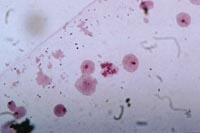

Bộ nhiễm sắc thể của muỗi An.minimus |

Bằng kỹ thuật phân tích kiểu nhân giai đoạn kỳ giữa (Metaphase karyotype) kết hợp với kỹ thuật điện di enzyme, C. A Green (1990) và Baimai .V (1996) kết luận rằng An. minimus là một phức hợp loài đồng hình. Ở Trung Quốc người ta cũng đã phát hiện thấy có hai dạng di truyền An. minimus A và An. minimus B, hai dạng này khác nhau về tập tính và vai trò truyền bệnh (Baimai .V, Harison B.A. and Nkavachara V, 1980).

Ở muỗi, không phải cá thể nào cũng có khả năng truyền bệnh sốt rét. Người ta thấy rằng, ở loài muỗi An. minimus (2n=6) thì có các cặp nhiễm sắc thể thường (autosome chromosome) rất giống nhau hệt nhau, riêng cặp nhiễm sắc thể giới tính (sex chromosome) là cân tâm (Metacentric chromosome), còn muỗi truyền bệnh sốt rét có nhiễm sắc thể giới tính tâm mút (Subtelocentric chromosome).

- Soi tìm tế bào trên kính hiển vi ở vật kính 10X, chuyển sang vật kính 40X để soi tìm tế bào có bộ nhiễm sắc thể 2n =6. Các bộ nhiễm sắc thể được phân tích trực tiếp trên vật kính 100X hoặc qua ảnh chụp.

- Phân biệt các cặp nhiễm sắc thể thường (autosome) với cặp nhiễm sắc thể giới tính (sex-chromosome). Hai cặp nhiễm sắc thể thường bắt màu nhạt, một cặp nhiễm sắc thể giới tính bắt màu đậm hơn.